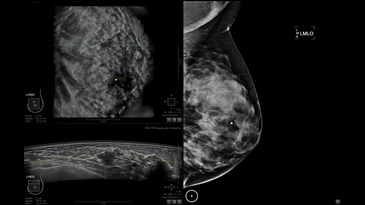

GE INVENIA ABUS – это современный УЗИ аппарат, который создан для точной и эффективной диагностики сканирования с высокой плотностью молочных желез. Выявляемость патологий раковых и предраковых стадий заболевания составляет 55%, что в конечном счете позволяет ставить врачу точные и своевременные диагнозы. Традиционные методы использования маммографии не показывают такой выявляемости, ограничиваясь лишь 3-38%.

УЗИ-аппарат GE INVENIA ABUS позволяет проводить максимально операторонезависимые процедуры, что значительно снижает риск неправильной постановки диагноза и сопутствующие издержки на обработку информации. Система готовит отчет в течение 3-х минут после сканирования, это безусловное преимущество по сравнению с обычным УЗИ сканером.

Данное устройство классифицируется, как стационарное, используемое в многопрофильных клиниках, женских консультациях, медицинских центрах. Вес без учета дополнительного оборудования составляет 105 кг. Удобная колесная база позволяет оперативно маневрировать в ограниченных пространствах, в том числе передвигать устройство в коридорах клиники. Большой 17-ти дюймовый монитор с широкими углами обзора выводит максимально качественную картинку в формате Full HD.